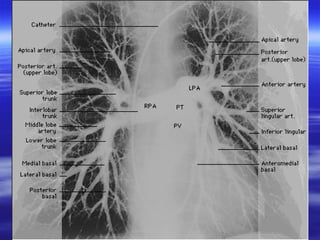

SSeeggmmeennttaall aannaattoommyy ooff tthhee lluunngg

Truncus anterior

Interlobar artery

Basal trunk

 In the cceennttrraall ppoorrttiioonnss ooff tthhee lluunnggss,, tthhee

uuppppeerr lloobbee aarrtteerriieess aarree ggeenneerraallllyy cceennttrraall ttoo

tthheeiirr aassssoocciiaatteedd bbrroonncchhii;; aanndd tthhee mmiiddddllee aanndd

lloowweerr lloobbee aanndd lliinngguullaarr aarrtteerriieess aarree

ggeenneerraallllyy ppeerriipphheerraall ttoo tthheeiirr aassssoocciiaatteedd

bbrroonncchhii ((1122)).. TThhee ppuullmmoonnaarryy vveeiinnss aarree

ggeenneerraallllyy aanntteerriioorr ttoo tthhee aarrtteerriieess eexxcceepptt iinn

tthhee rriigghhtt uuppppeerr lloobbee..

Truncus anterior Interlobarartery Basal trunk

 In thecceennttrraall ppoorrttiioonnss ooff tthhee lluunnggss,, tthhee uuppppeerr lloobbee aarrtteerriieess aarree ggeenneerraallllyy cceennttrraall ttoo tthheeiirr aassssoocciiaatteedd bbrroonncchhii;; aanndd tthhee mmiiddddllee aanndd lloowweerr lloobbee aanndd lliinngguullaarr aarrtteerriieess aarree ggeenneerraallllyy ppeerriipphheerraall ttoo tthheeiirr aassssoocciiaatteedd bbrroonncchhii ((1122)).. TThhee ppuullmmoonnaarryy vveeiinnss aarree ggeenneerraallllyy aanntteerriioorr ttoo tthhee aarrtteerriieess eexxcceepptt iinn tthhee rriigghhtt uuppppeerr lloobbee..